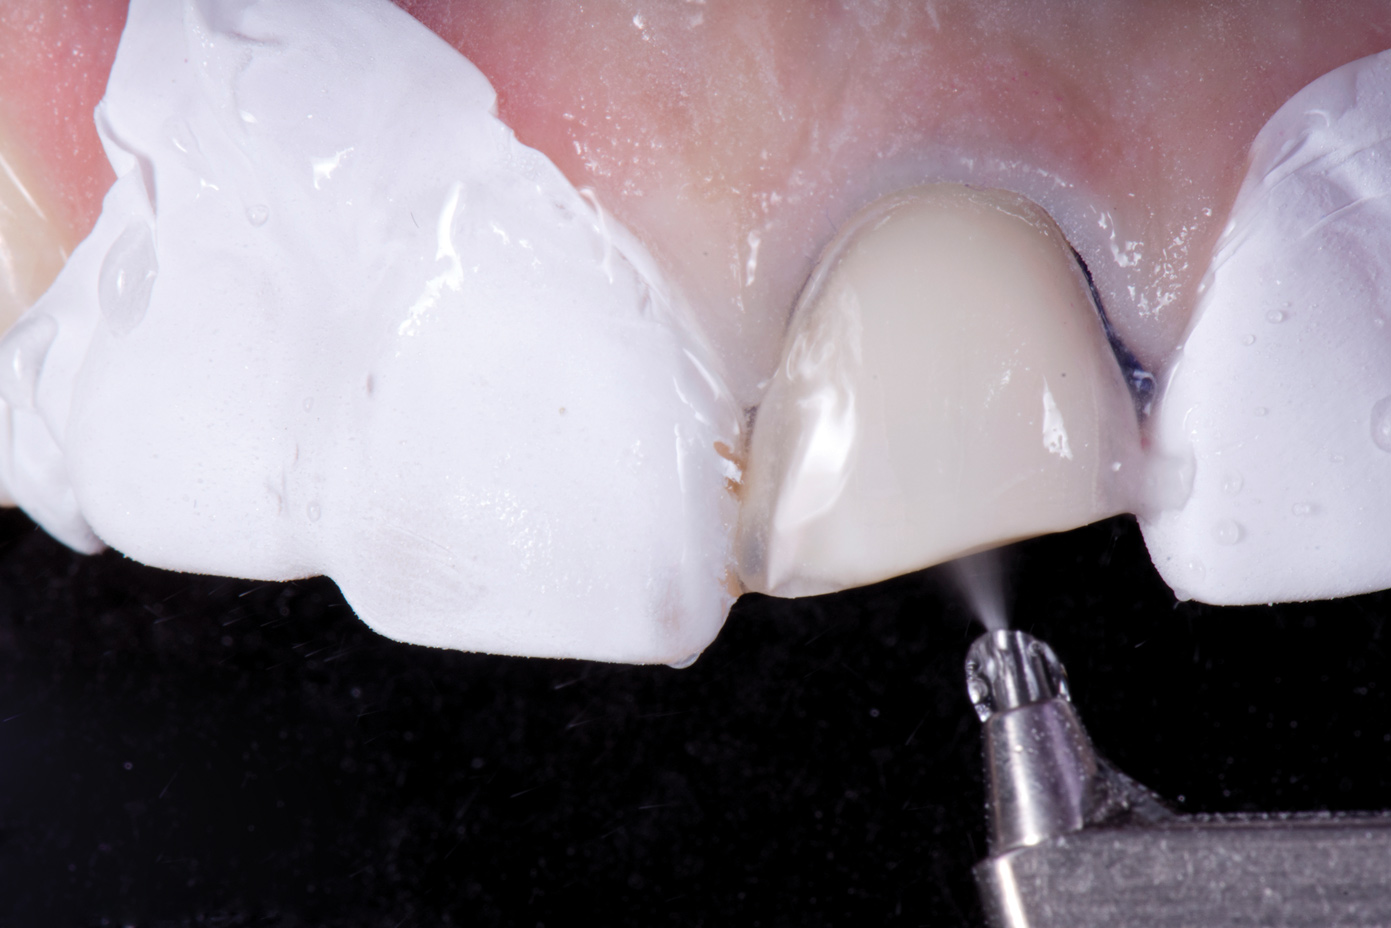

Fig 11. Air abrasion of enamel.

Figure 11

Fig 12. Matte surface of clean enamel after air abrasion prior to bonding.

Figure 12

With these limitations acknowledged, visual inspection of tooth preparations after air abrasion reveals that this modality is effective in removing remnant restorative materials, stains, and temporary cement, leaving a clean, matte surface for bonding (Figure 11 through Figure 14). Air abrasion also can smooth the internal aspects of a cavity preparation to help enable better adaptation of the restorative material (Figure 15 and Figure 16). The technique-sensitive nature of adhesive bonding may justify this extra procedure to ensure a clean, smooth preparation.